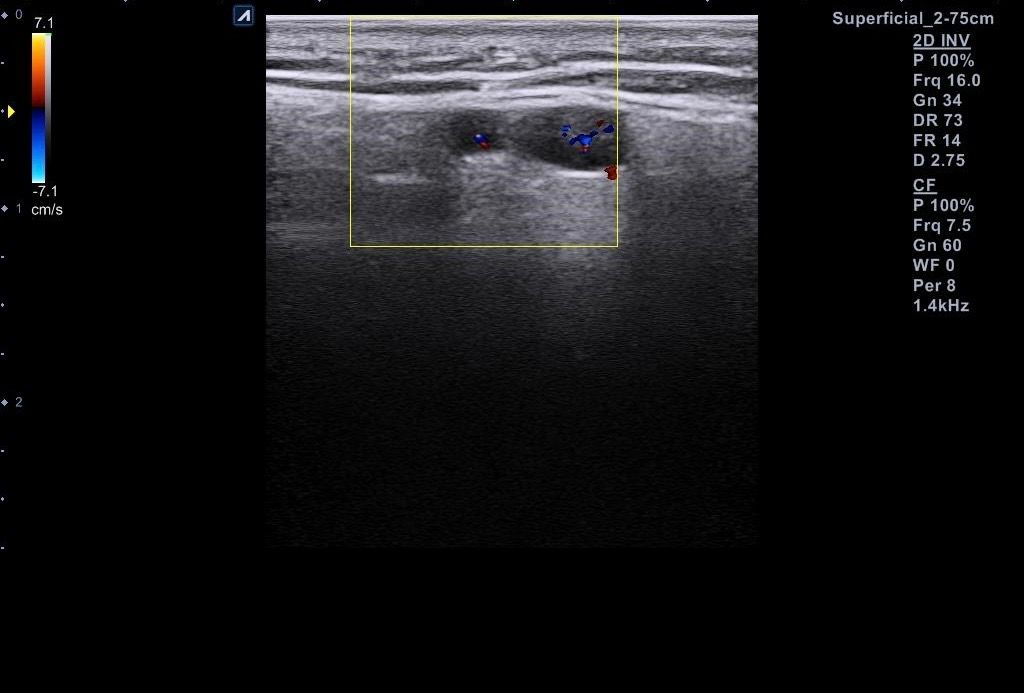

근데 병원에서 지방종이 아니라 임파선 같다고 일단 초음파 본다고 하시고 초음파를 봤는데 의사선생님이 귀 옆에 있는 임파선은 괜찮은데 아래에 있는 임파선이 초음파로 볼때 모양이랑 뭐가 조금 이상하다고 하시면서 대학병원가보라고 소견서를 써주셨습니다 (소견서랑 초음파사진 첨부할게요) 설명들을때 기억상으로는 1 2번째 초음파사진이 귀 아래였던 거 같아요

• 4번 째 사진